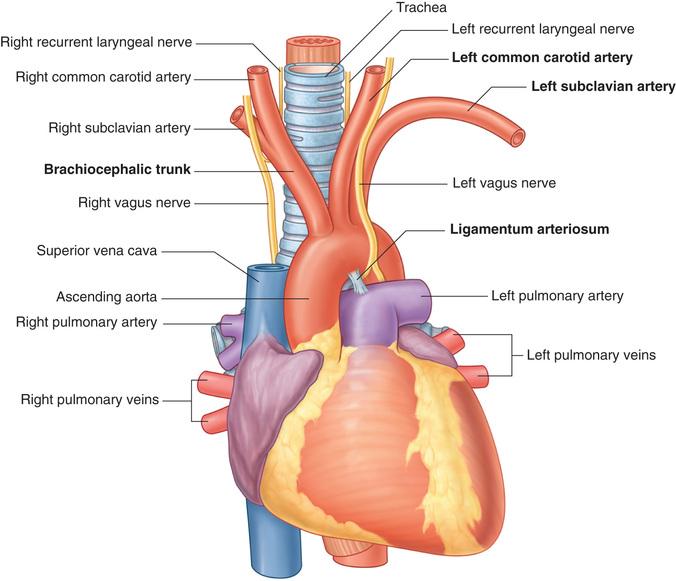

Fig 3.04: Arcus aortae

omslagplooi pericardium trachea esophagus tr. pulmonalis lig. arteriosum isthmus aortae (vernauwing lumen t.h.v. lig. arteriosum) linker n vagus (X) -

linker n vagus > linker n laryngeus recurrens = n recurrens

zijtakken arcus aorta

-

tr. brachiocephalicus

a subclavia dextra a carotis communis dextra

a carotis communis sinistra a subclavia sinistra (a thyroidea ima)